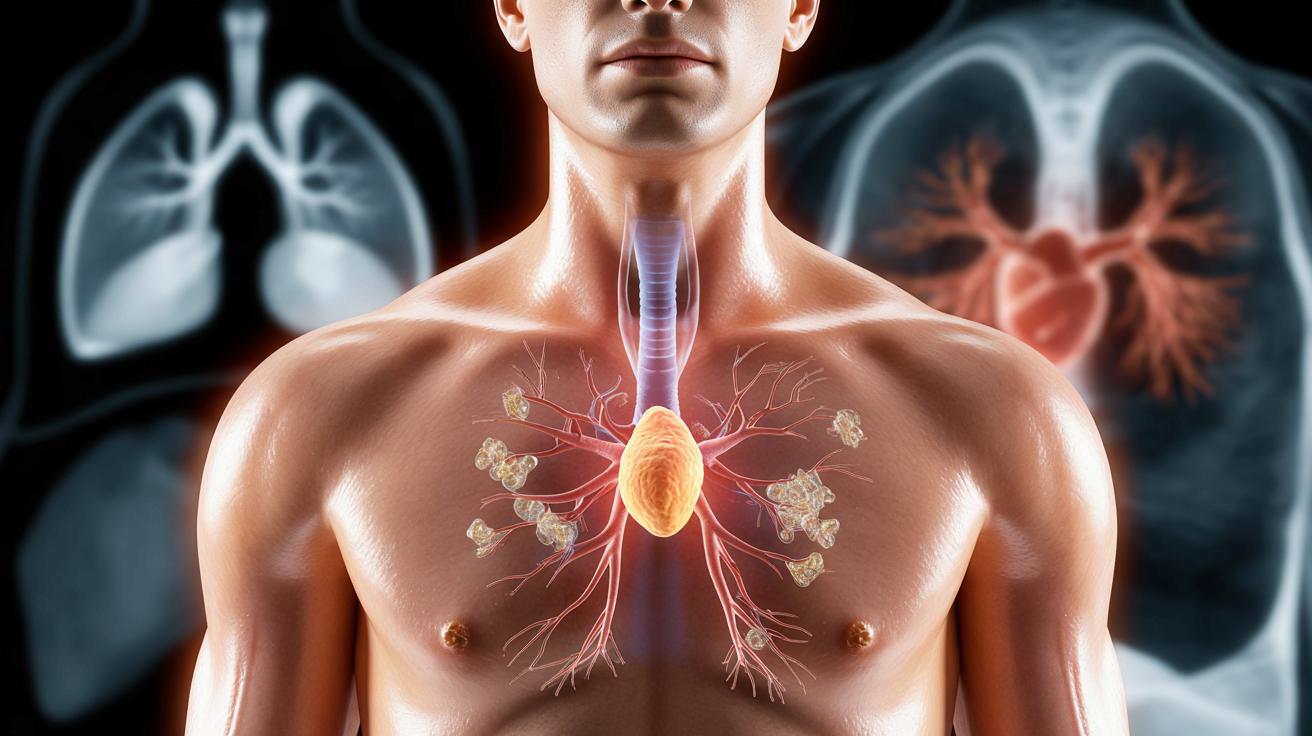

Niewielki gruczoł pod mostkiem, który może chronić przed rakiem

Mały narząd ukryty za mostkiem zaczyna interesować lekarzy bardziej niż kiedykolwiek – jego kondycja może decydować o długości życia.

Grasica – zapomniany organ od odporności

Grasica to niewielki gruczoł położony w klatce piersiowej, tuż za mostkiem. Należy do układu odpornościowego i odpowiada za dojrzewanie limfocytów T – komórek, które rozpoznają i niszczą komórki zakażone oraz nowotworowe.